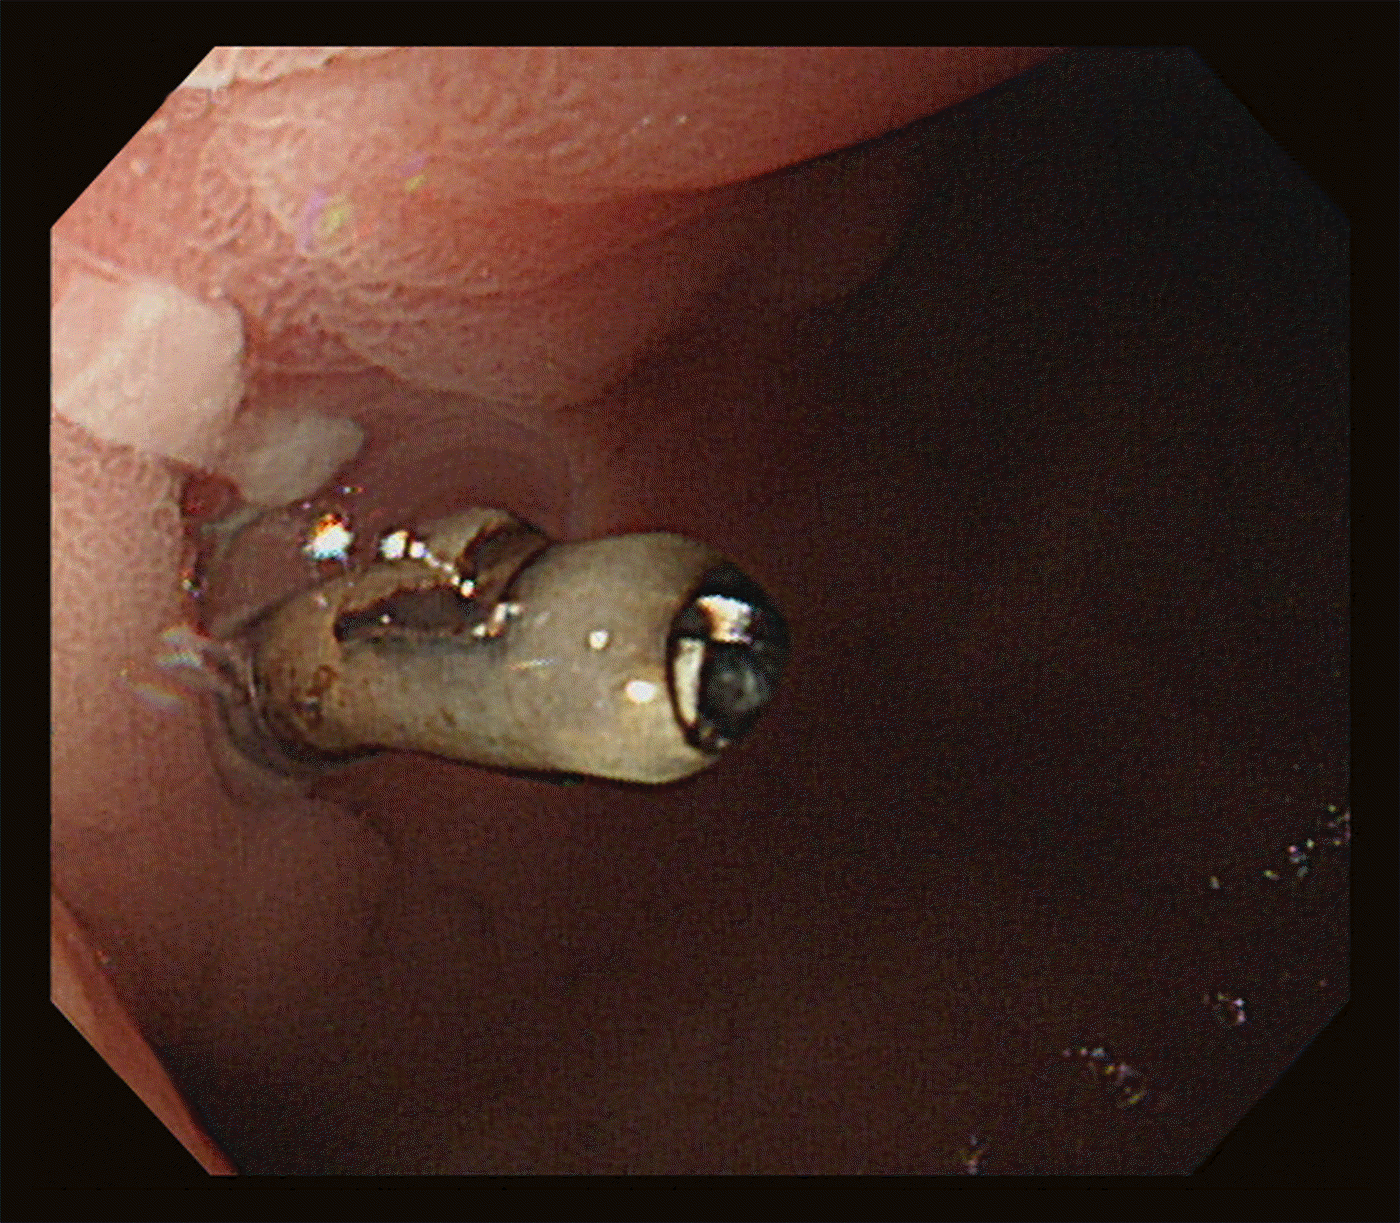

A 68-year-old man presented with recurrent melena for 1 year. A 9.6-cm-sized cholangiocarcinoma in the right liver lobe was identified 2 years prior, and the patient underwent right trisectionectomy with caudate lobectomy. Postoperative doppler ultrasonography and computed tomography (CT) demonstrated narrowing of the portal vein anastomosis site, and stent insertion was performed. He had no history of medication use, including nonsteroidal anti-inflammatory and anti-acid drugs. However, 1 year postoperatively, he was re-admitted to an emergency center with hematemesis. Upper endoscopy revealed an active ulcer and exposed vessels in the duodenal bulb (Fig. 1A). Bleeding was controlled by hemoclipping, and rapid urease test results were negative. The patient experienced intermittent, small-volume melena 8 months after bleeding control, and endoscopic evaluation was performed again. The ulceration persisted in the duodenal bulb, and a metallic material was observed, which was suspected to be stent exposure (Fig. 1B). A recent CT scan confirmed complete thrombotic occlusion of the portal vein stent, and it was determined that the previous surgery resulted in adhesion between the stent and duodenum (Fig. 2). The ulcer worsened due to portal stent exposure. The patient was treated conservatively and was discharged with ulcer medications. A follow-up endoscopy revealed an almost completely healed ulceration (Fig. 3).

Stent migration into the gastrointestinal tract can cause recurrent bleeding,1,2 and portal venous stent migration into the duodenum following liver resection is rare. If repeated duodenal ulcerations persist, with or without stent exposure, the cause should be assessed. Conservative treatment may be more effective, compared with stent removal. Herein, we describe an extremely rare case of refractory duodenal ulcer caused by portal stent exposure.